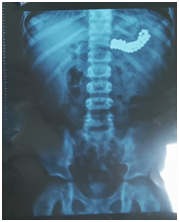

↑腹部X光片

前后3次,医生们一共取出10颗磁力珠。这时,孩子的胃里,剩余的磁力珠分开成一个平面,拉成了长线,医生慢慢套住磁力珠头端,又慢慢牵引,一次性又取出了51颗。

最后,复查腹部平片的结果显示,小朋友消化道内的磁力珠已全部取出。